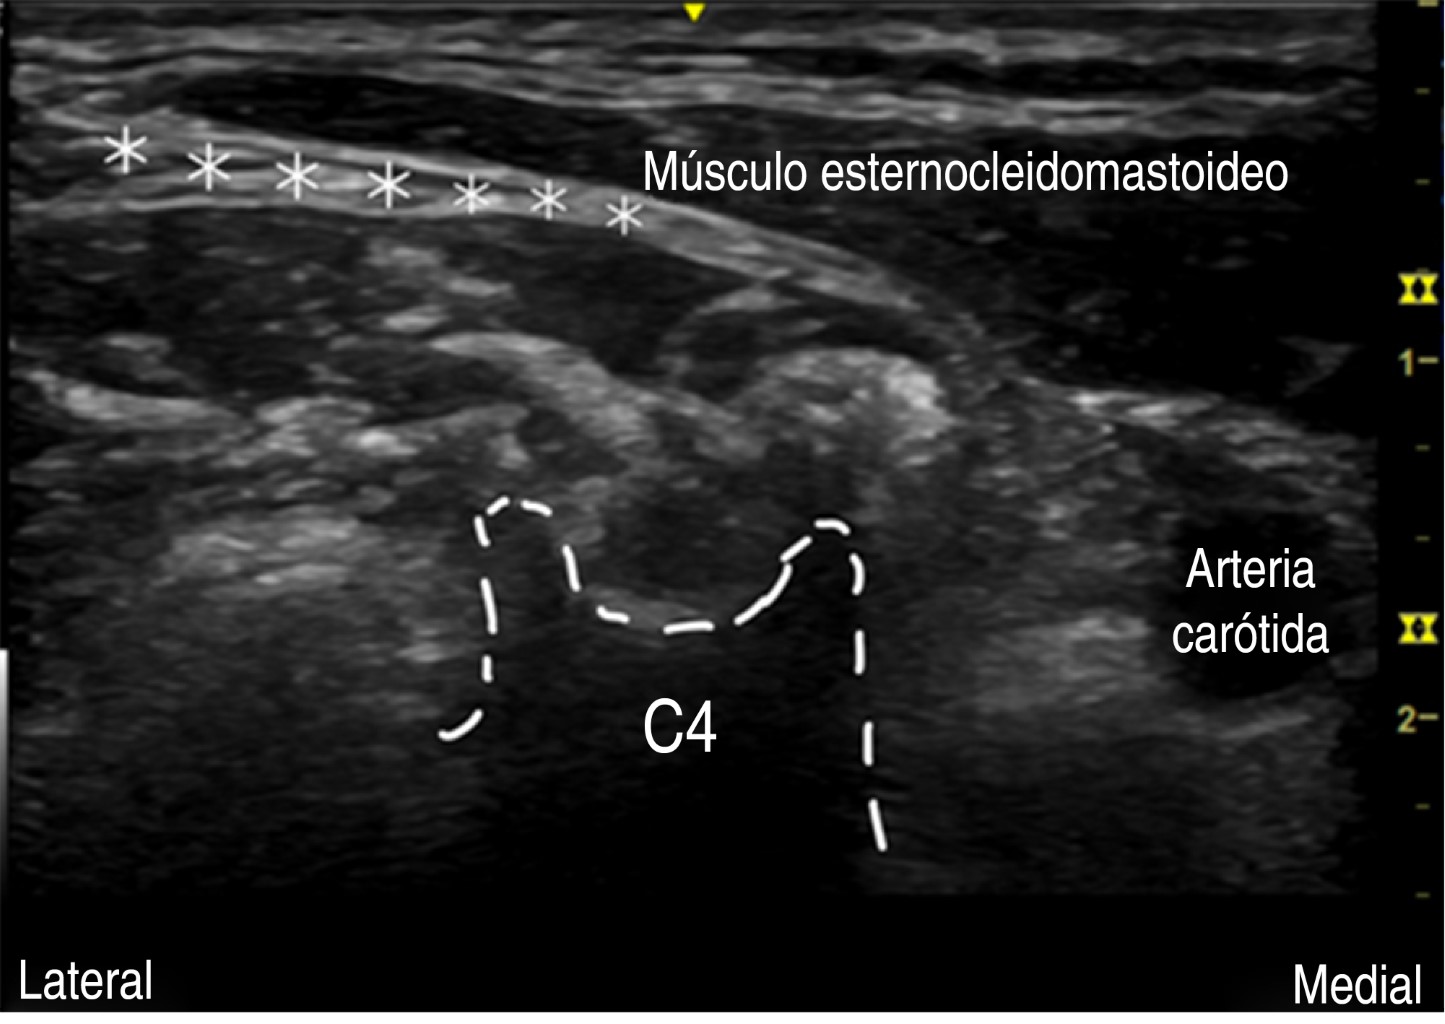

Figure 1